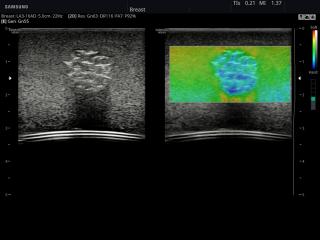

- Модуль Elastoscan - программы эластографии (качественная оценка) для исследований щитовидной железы, молочной железы у женщин и предстательной железы у мужчин.

Примеры клинических изображений УЗИ аппарата hs40 A-RUS (Samsung Medison)